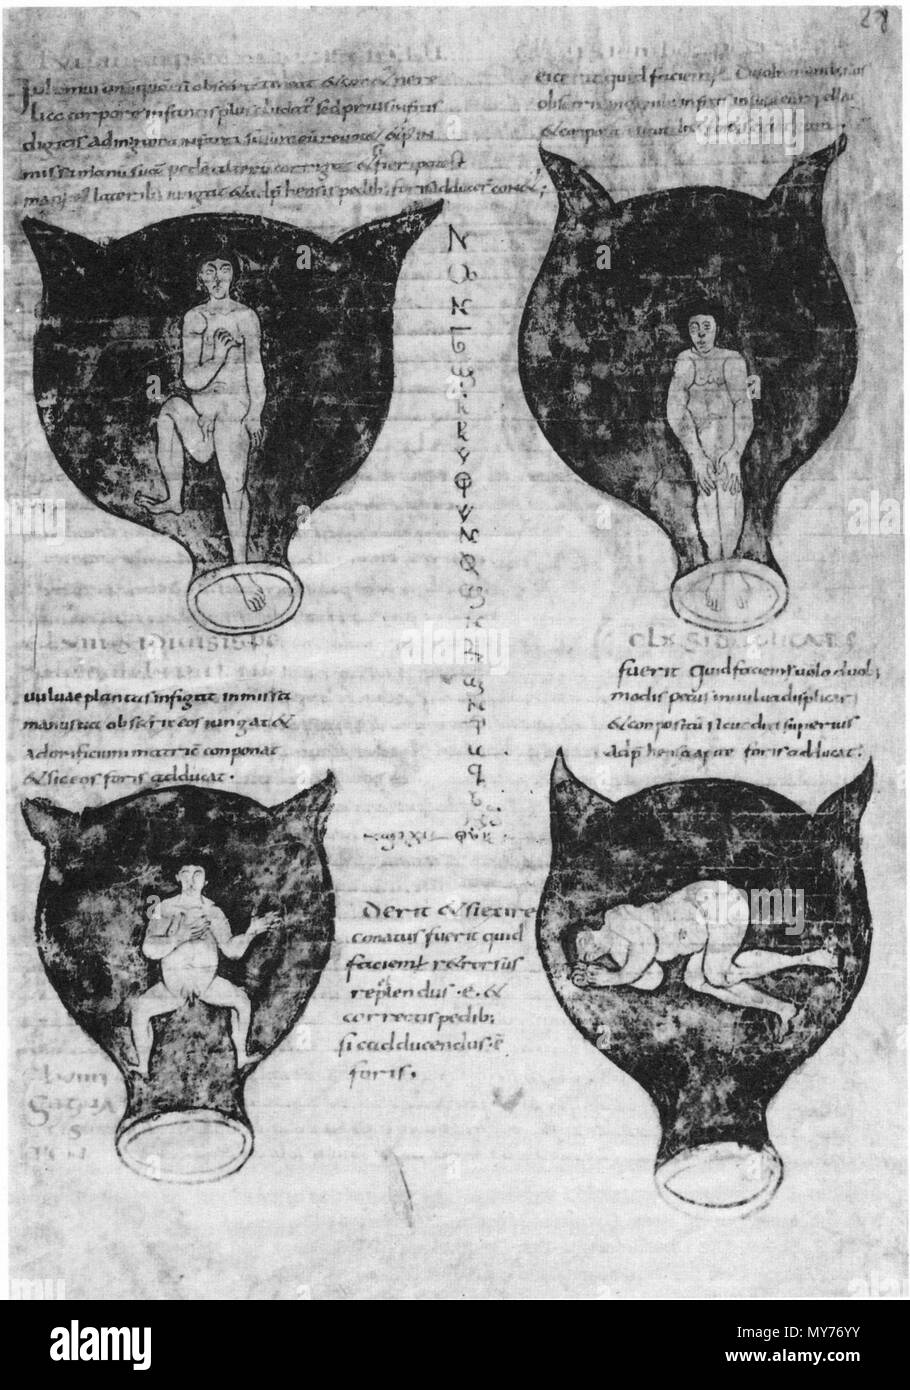

Foetal positions BR 3701 15 28r Stock Photohttps://www.alamy.com/image-license-details/?v=1https://www.alamy.com/stock-photo-foetal-positions-br-3701-15-28r-142854616.html

Foetal positions BR 3701 15 28r Stock Photohttps://www.alamy.com/image-license-details/?v=1https://www.alamy.com/stock-photo-foetal-positions-br-3701-15-28r-142854616.htmlRMJ8BGEG–Foetal positions BR 3701 15 28r

. English: Soranus of Ephesus, Gynaecology, in a Latin version of Late Antiquity: positions of the embryo in the uterus. The illustrations in this medieval manuscript are probably based on drawings by Soranus. Brussels, Bibliothèque Royale, Codex 3714, fol. 28r. Deutsch: Soranos von Ephesos, Gynäkologie, in einer spätantiken lateinischen Bearbeitung: Darstellungen von Kindslagen (Embryonen im Uterus). Die Abbildungen in dieser mittelalterlichen Handschrift gehen wohl ursprünglich auf Zeichnungen des Soranos zurück. Bruxelles, Bibliothèque Royale, Codex 3714, fol. 28r. circa 900. Soranus of Eph Stock Photohttps://www.alamy.com/image-license-details/?v=1https://www.alamy.com/english-soranus-of-ephesus-gynaecology-in-a-latin-version-of-late-antiquity-positions-of-the-embryo-in-the-uterus-the-illustrations-in-this-medieval-manuscript-are-probably-based-on-drawings-by-soranus-brussels-bibliothque-royale-codex-3714-fol-28r-deutsch-soranos-von-ephesos-gynkologie-in-einer-sptantiken-lateinischen-bearbeitung-darstellungen-von-kindslagen-embryonen-im-uterus-die-abbildungen-in-dieser-mittelalterlichen-handschrift-gehen-wohl-ursprnglich-auf-zeichnungen-des-soranos-zurck-bruxelles-bibliothque-royale-codex-3714-fol-28r-circa-900-soranus-of-eph-image188858543.html

. English: Soranus of Ephesus, Gynaecology, in a Latin version of Late Antiquity: positions of the embryo in the uterus. The illustrations in this medieval manuscript are probably based on drawings by Soranus. Brussels, Bibliothèque Royale, Codex 3714, fol. 28r. Deutsch: Soranos von Ephesos, Gynäkologie, in einer spätantiken lateinischen Bearbeitung: Darstellungen von Kindslagen (Embryonen im Uterus). Die Abbildungen in dieser mittelalterlichen Handschrift gehen wohl ursprünglich auf Zeichnungen des Soranos zurück. Bruxelles, Bibliothèque Royale, Codex 3714, fol. 28r. circa 900. Soranus of Eph Stock Photohttps://www.alamy.com/image-license-details/?v=1https://www.alamy.com/english-soranus-of-ephesus-gynaecology-in-a-latin-version-of-late-antiquity-positions-of-the-embryo-in-the-uterus-the-illustrations-in-this-medieval-manuscript-are-probably-based-on-drawings-by-soranus-brussels-bibliothque-royale-codex-3714-fol-28r-deutsch-soranos-von-ephesos-gynkologie-in-einer-sptantiken-lateinischen-bearbeitung-darstellungen-von-kindslagen-embryonen-im-uterus-die-abbildungen-in-dieser-mittelalterlichen-handschrift-gehen-wohl-ursprnglich-auf-zeichnungen-des-soranos-zurck-bruxelles-bibliothque-royale-codex-3714-fol-28r-circa-900-soranus-of-eph-image188858543.htmlRMMY76YY–. English: Soranus of Ephesus, Gynaecology, in a Latin version of Late Antiquity: positions of the embryo in the uterus. The illustrations in this medieval manuscript are probably based on drawings by Soranus. Brussels, Bibliothèque Royale, Codex 3714, fol. 28r. Deutsch: Soranos von Ephesos, Gynäkologie, in einer spätantiken lateinischen Bearbeitung: Darstellungen von Kindslagen (Embryonen im Uterus). Die Abbildungen in dieser mittelalterlichen Handschrift gehen wohl ursprünglich auf Zeichnungen des Soranos zurück. Bruxelles, Bibliothèque Royale, Codex 3714, fol. 28r. circa 900. Soranus of Eph